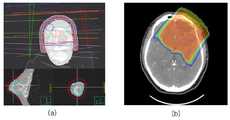

도 2는 방사선 세기 변조체의 종류를 예시적으로 나타내는 도면으로서, 도 2의 (a)는 X선을 선원으로 하는 방사선 치료를 위해 설계된 방사선 세기 변조체를 나타내며, 도 2의 (b)는 양성자를 선원으로 하는 방사선 치료를 위해 설계된 방사선 세기 변조체를 나타낸다.2 (a) and 2 (b) show a radiation intensity modulator designed for radiation therapy using X-ray as a source. FIG. 2 (b) The radiation intensity modulator designed for radiation therapy.

도 3은 밀도 매트릭스로 표현된 선량 변조 정보와 3차원 구조체 정보를 나타내는 도면으로서, 도 3의 (a)는 3차원 구조체 형태로 설계된 방사선 세기 변조체를 나타내며, 도 3의 (b)는 선량 변조 정도를 나타내는 밀도 매트릭스 형태로 설계된 방사선 세기 변조체를 나타낸다.FIG. 3 shows dose modulation information and three-dimensional structure information represented by a density matrix. FIG. 3 (a) shows a radiation intensity modulator designed in the form of a three-dimensional structure, and FIG. 3 (b) Of the radiation intensity modulator in the form of a density matrix.

도 9는 제작된 방사선 세기 변조체를 나타내는 도면이다. 도 9의 (a)는 3차원 구조체 형태로부터 제작된 방사선 세기 변조체를 나타내며, 도 9의 (b)는 선량 변조 정도를 나타내는 밀도 매트릭스 형태로부터 제작된 방사선 세기 변조체를 나타낸다.

9 is a view showing a manufactured radiation intensity modulator. 9 (a) shows a radiation intensity modulator manufactured from the shape of a three-dimensional structure, and FIG. 9 (b) shows a radiation intensity modulator manufactured from a density matrix shape showing a degree of dose modulation.